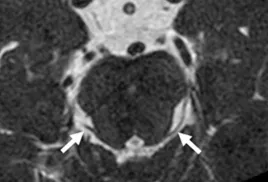

A Steady-state free precession (SSFP) axial image showing the olfactory nerves (arrows).

A Steady-state free precession (SSFP) axial image showing the optic nerves (arrows).